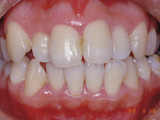

症例3:咬合(前歯が閉じない)

治療前

治療後